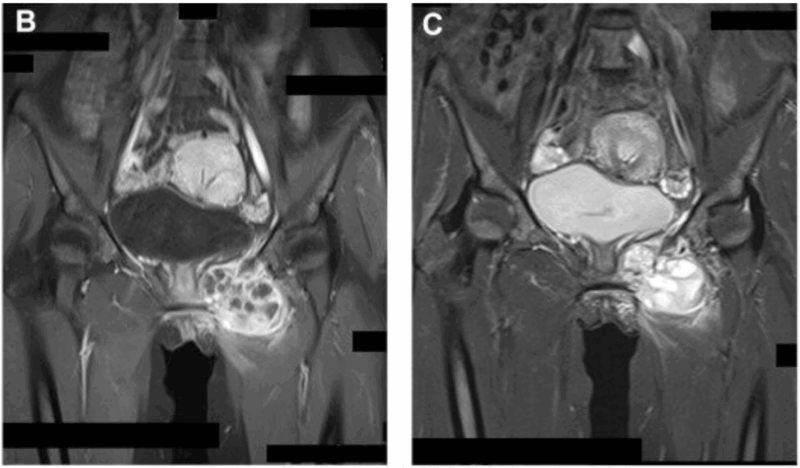

恥骨を破壊した腫瘍が骨の外に出て, 前下方の筋肉の中に進展しています.

また, MRIを見ると, 恥骨内の病変が骨を破壊して, 周囲の筋肉に進展していたので, 骨肉腫という悪性骨腫瘍が強く疑われました.